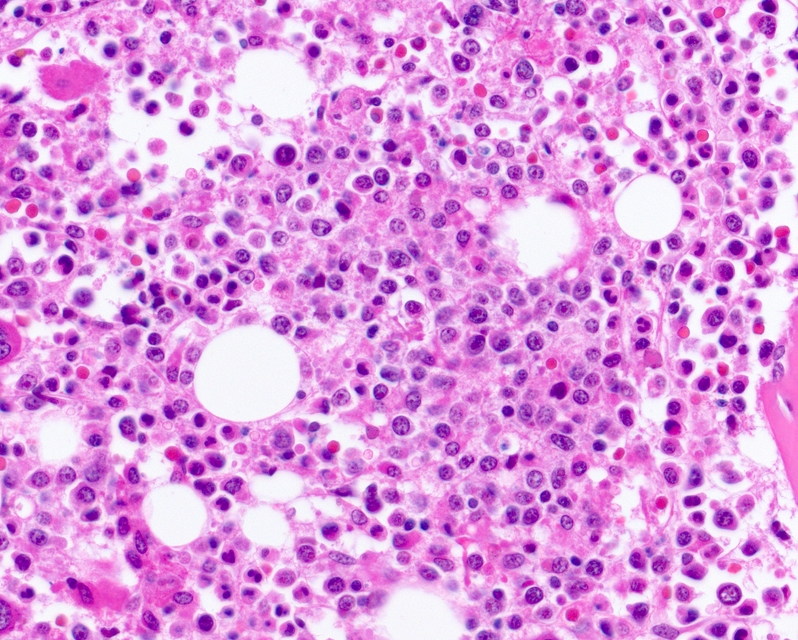

В нишах костного мозга располагаются гемопоэтические стволовые клетки, подпитывающие постоянную замену эритроцитов на новые. Лечение заболевания связано именно с восполнением запаса способных к самообновлению клеток — репродукция стволовых клеток может спасать больных с лейкемией.

Обновление в искусственных условиях возможно, но для этого требуется идеальное сходство пористой структуры искусственного костного мозга с настоящим, похожим на губку. Ученым удалось добиться требуемого сходства благодаря белковым «строительным блокам». К этим блокам могут прикрепляться клетки. Кроме того, частью структуры стали другие клетки, расположенные в нишах костного мозга.

Может ли искусственный мозг заменить настоящий, ученые проверили в ходе эксперимента с пуповинной кровью. Из крови выделили стволовые клетки и внедрили их в синтезированный мозг. Через несколько дней ученые убедились, что за это время выросли новые клетки. У большинства клеток сохранились естественные свойства, чего не происходит, если клетки выращивают в условиях лаборатории.